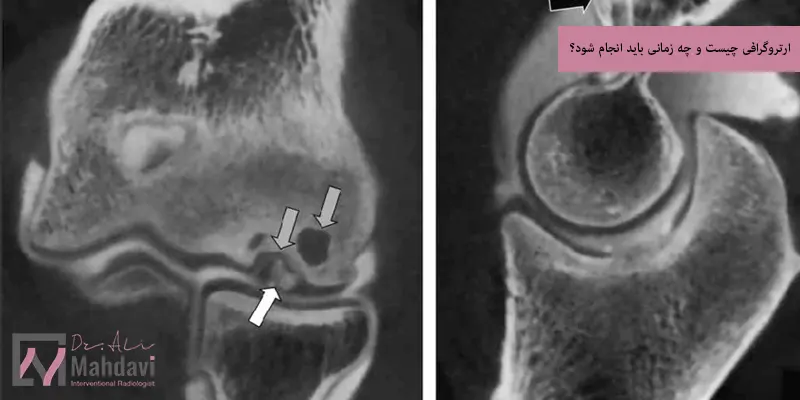

ارتروگرافی چیست؟

ارتروگرافی نوعی روش تصویربرداری تخصصی است که برای بررسی دقیق مفاصل بدن به کار میرود و در این روش، پزشک ماده حاجب یک رنگ مخصوصی که در عکس برداری قابل مشاهده است را به داخل فضای مفصل تزریق میکند تا جزئیات ساختارهای داخلی مانند غضروف، رباط ها، تاندون ها و کپسول مفصلی بهتر دیده شوند و سپس با استفاده از تصویربرداری هایی مانند اشعه ایکس، سی تی اسکن یا امآرآی تصاویر دقیقی از مفصل گرفته میشود، ارتروگرافی به ویژه برای بررسی مفاصل شانه، زانو، لگن و مچ بسیار کاربرد دارد و به تشخیص مشکلاتی مانند پارگی رباط ها یا آسیب غضروفی کمک میکند.

امآر آرتروگرافی

در این نوع، پس از تزریق ماده حاجب مخصوص، از دستگاه MRI برای تصویربرداری استفاده میشود، امآر آرتروگرافی دقیق ترین نوع ارتروگرافی است و جزئیات بافت های نرم مانند رباط ها، غضروف ها و تاندون ها را با وضوح بالا نشان میدهد، این روش برای تشخیص آسیب های مفصل شانه، لگن و زانو به ویژه در ورزشکاران بسیار مؤثر است.